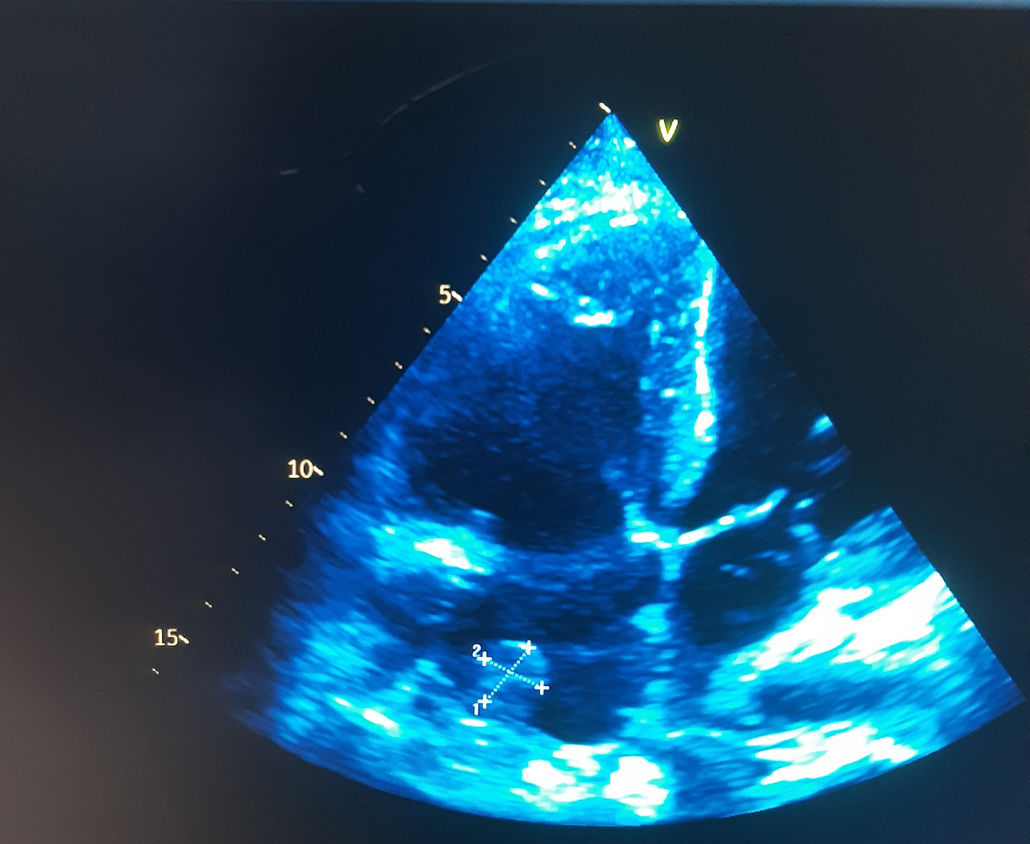

Los hemocultivos de control persistieron positivos para S. aureus en dos tomas posteriores, negativizándose en los controles subsiguientes tras el ajuste del tratamiento antibiótico. Luego de tres semanas de terapia dirigida, el ecocardiograma transtorácico de control mostró persistencia de la imagen nodular adherida a la válvula de Eustaquio, con dimensiones similares a las previamente informadas, sin evidencia de incremento en su tamaño ni de complicaciones adicionales (fig. 2). La paciente completó el esquema de antibióticos endovenosos prolongados, con mejoría progresiva de la disnea y estabilización de los parámetros inflamatorios, motivo por el cual fue dada de alta con tratamiento antibiótico oral para completar tres semanas adicionales con trimetoprim/sulfametoxazol. No se realizó ecocardiografía transesofágica debido a que el ecocardiograma transtorácico ofrecía una ventana acústica adecuada y permitía una visualización satisfactoria de las estructuras implicadas, por lo que se consideró suficiente para el seguimiento.